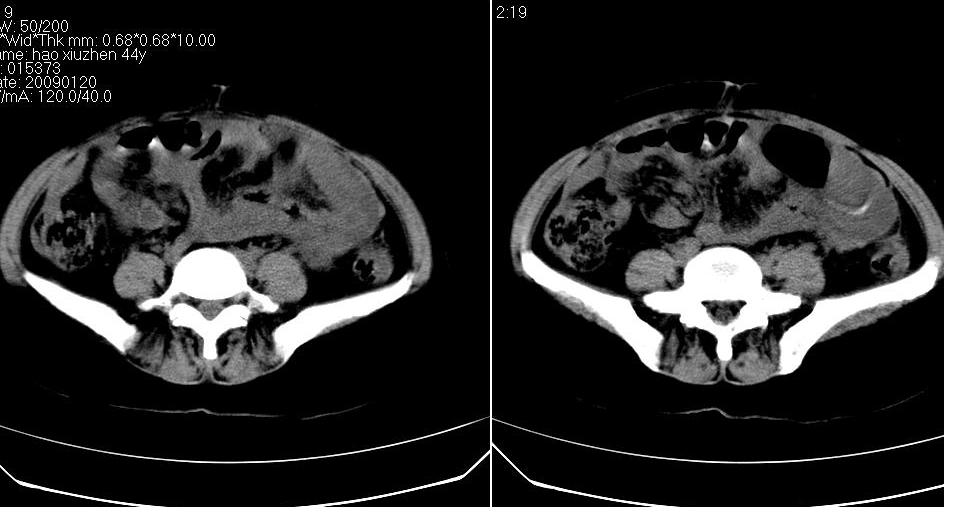

标题: CT17773B盆腔CT平扫

女 44岁,于ct17773号病例同一个病人。有结果我会尽快告诉大家。

盆腔及腹腔积液,原因待查。

结核性腹膜炎可能,